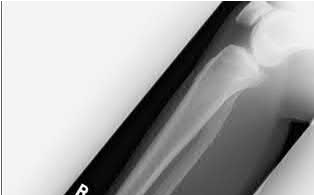

Buttress plating is most appropriate in which of the following clinical situations?

Buttress plating is appropriate for a Shatzker Type I (see illustration C), as it can prevent collapse and axial deformity from shear or bending forces.

Figure B demonstrates an isolated medial femoral condyle fracture. Lateral locked plating is not an appropriate technique for this fracture.

The fracture shown in Figure B is an AO B type (partial articular fracture). This fracture is best treated with open reduction internal fixation through a medial approach, with lag screw and buttress plate fixation.

Figures A, C, D and E show supracondylar distal femur fractures that can be treated with ORIF with a fixed-angle device such as lateral locked plating.